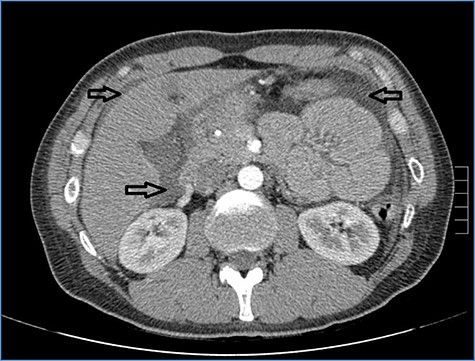

Abdominal CT scan showing distention, bundling and thickening of some small bowel loops in the left quadrant (arrow).

fluid collection in the peritoneal cavity. Subsequent CT confirmed the presence of diffuse fluid collection in the peritoneal cavity (Fig. 1) but no free air, with distention, bundling and thickening of some small bowel in the left quadrant (Fig. 2). The patient was therefore admitted for supporting therapy (intravenous fluids and antibiotics) with the suspicion of cocaine-induced small bowel ischemia. Twelve hours later, signs and symptoms of diffuse peritonitis developed: worsening diffuse abdominal pain with rebound guarding at examination, a significant increase in WBCs count (16.15 × 103/μl) and neutrophilia (88%), lengthening of coagulation times (INR: 1.68; aPTT: 33.0 s) and increase in fibrinogen (430 mg/dl) and D-Dimer (2275 ng/ml). Therefore, urgent surgical exploration of the abdomen through a three-port open laparoscopic approach was performed, confirming the presence of 1200 ml of exudative fluid and fibrin clots (Fig. 3). Several adhesions between greater omentum, abdominal wall and small bowel underwent blunt dissection. Thorough exploration of the small bowel revealed two ischemic segments located at about 50 and 100 cm from the Treitz ligament (Fig. 4). The large bowel appeared normal. The existence of non-visible gastro-duodenal perforations was ruled out with the administration of 500 ml of saline with 20 ml of methylene blue through the nasogastric tube. An iv bolus of sodium heparin, 10 000 IU, was then administered, performing a 30-min peritoneal lavage with 5 l of saline solution at 37°C. After reaspiration of peritoneal lavage, a new complete exploration of the small bowel was performed, showing complete revascularization of the two ischemic small bowel segments (Fig. 5). Two tubular drainage tubes were placed in the left and right colic gutters. Culture examination of peritoneal exudate was positive for multi-sensitive Escherichia coli and Enterococcus, thus confirming bacterial translocation peritonitis. Postoperative therapy included the administration of iv piperacillin–tazobactam and subcutaneous low molecular weight heparin. Postoperative recovery was smooth, with oral feeding on the second postoperative day (POD), drainage removal on POD 3, complete bowel function restored on POD 4 and home discharge on POD 5. At 15- and 30-day-follow-up, the patient showed full recovery, being now followed by a specialized support structure for his drug abuse.